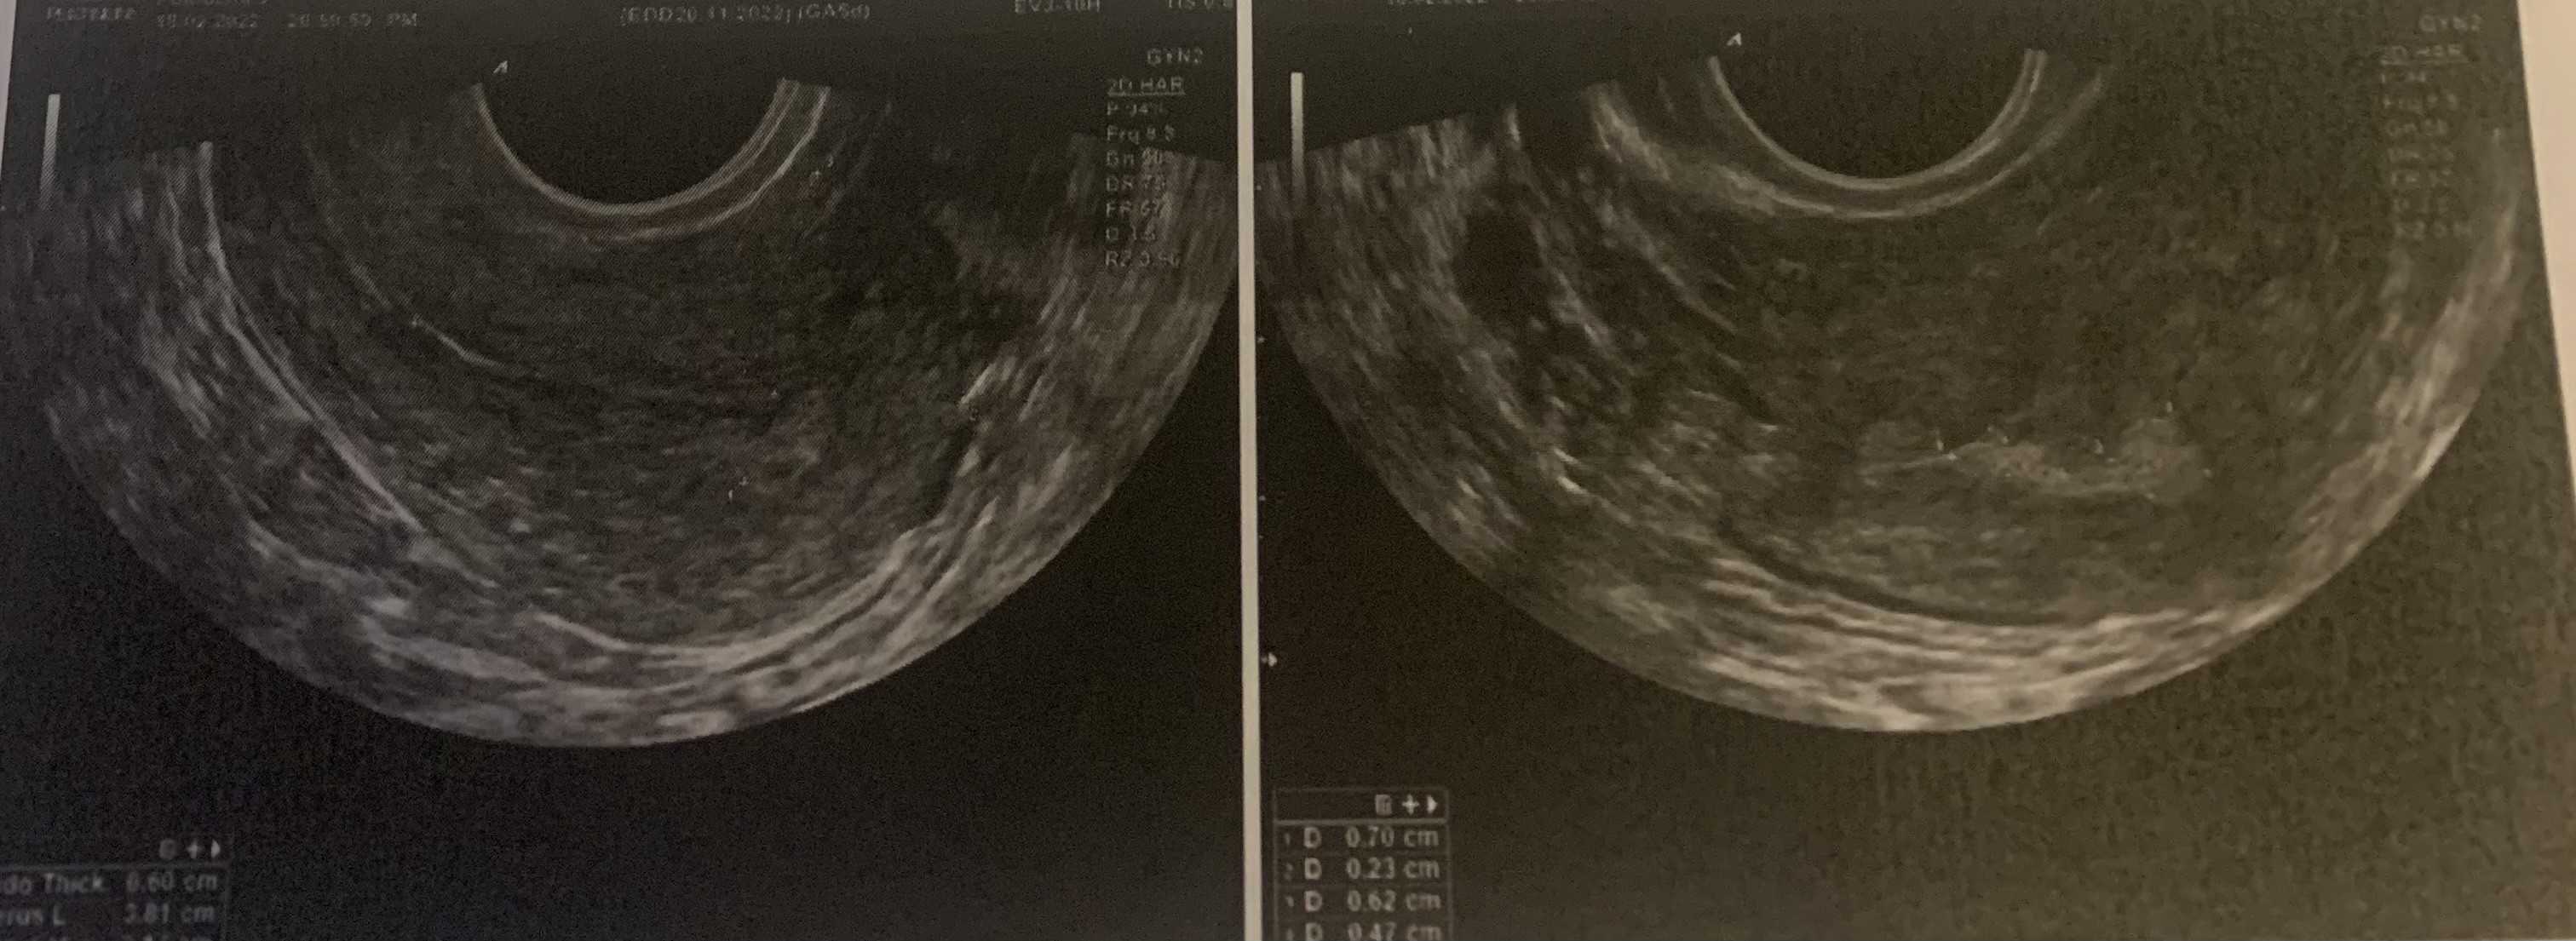

Staramy się z mężem trzeci miesiąc. Po dzisiejszej wizycie u ginekologa i usg wykryto u mnie dwa polipy endometrialne o średnicy 7x2mm i 6x5mm bez patologicznego unaczynienia.

Kurcze właśnie nie mam pojęcia gdzie są umiejscowione, lekarz nie powiedział a ja nie dopytałam, bo aż mnie wcięło gdy okazało się że są polipy... a niestety po zdjęciu usg nie mam pojęcia jak określić gdzie są zlokalizowane :/

Może któraś z was jest bardziej „ogarnięta” w rozróżnianiu tego :(

• 3A47B6A5-DDE2-44EB-853D-F553AC8A314E.jpeg

3A47B6A5-DDE2-44EB-853D-F553AC8A314E.jpeg

670,2 KB · Wyświetleń: 663